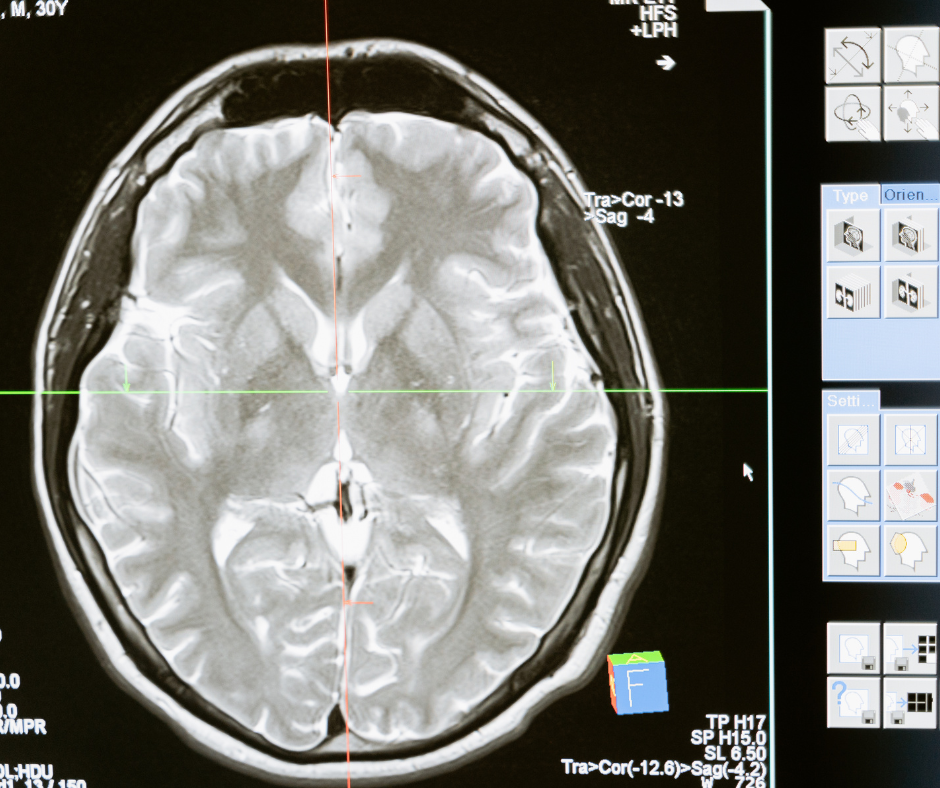

Offriamo soluzioni all'avanguardia per la diagnostica per immagini: sistemi TAC multistrato (da 16 a 128 slice) progettati per diagnosi rapide, alta risoluzione clinica e protocolli a dose ridotta.